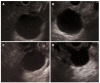

Cystic lesions of the pancreas are being diagnosed with increasing frequency, covering a vast spectrum from benign to malignant and invasive lesions. Numerous investigations can be done to discriminate between benign and non-evolutive lesions from those that require surgery. At the moment, there is no single test that will allow a correct diagnosis in all cases. Endoscopic ultrasound (EUS) morphology, cyst fluid analysis and cytohistology with EUS-guided fine needle aspiration can aid in this difficult diagnosis.